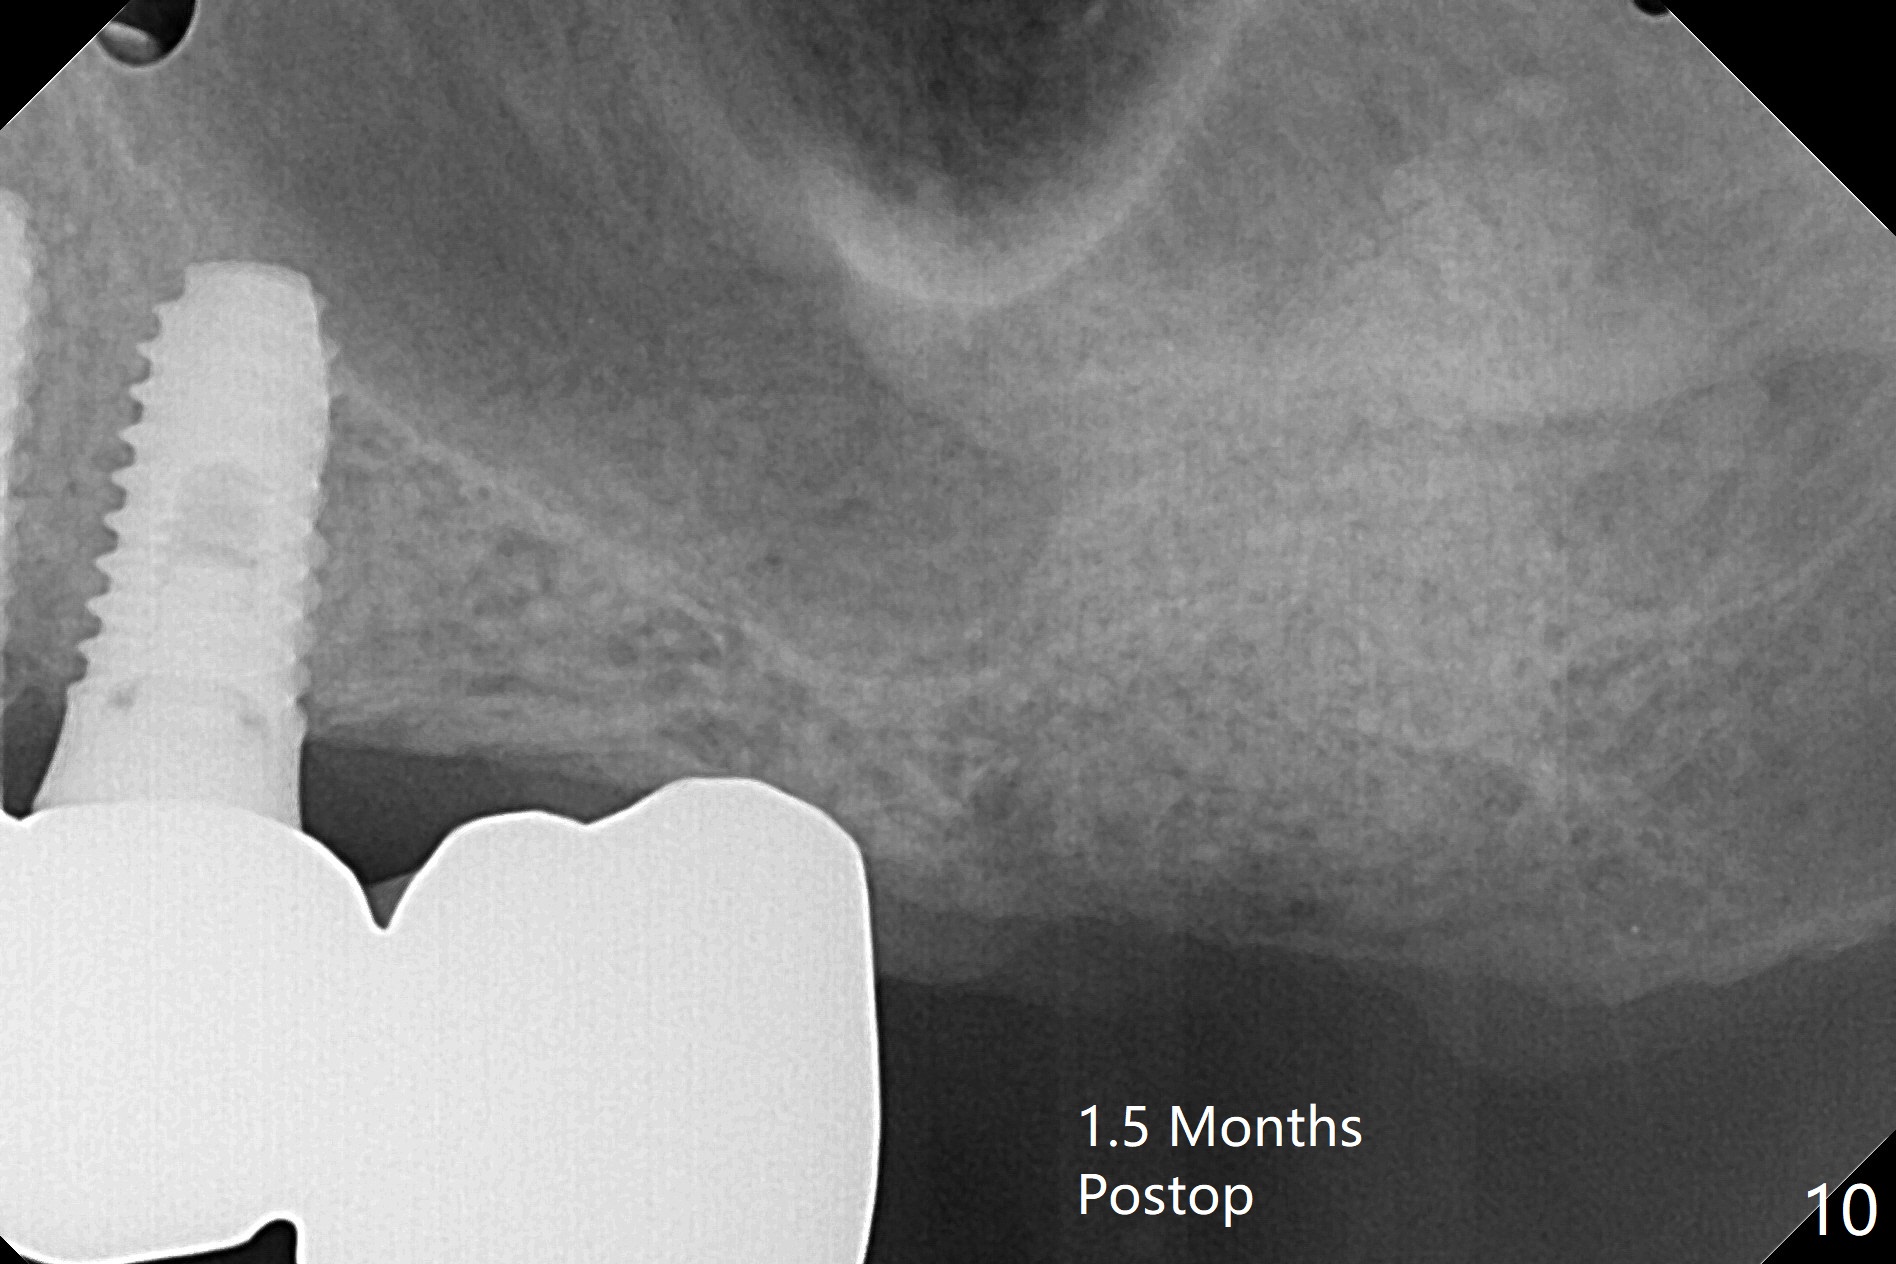

86岁男左上7折裂(图一),要求拔除,经过讨论(7拔除后,4-6悬臂桥可能断裂,对植体产生创伤,图二(左下7存在)),同意植骨。拔牙时发现中隔特别粗大(图三,五:S),三个牙槽窝根尖好像在中隔下面相互交通,擤鼻涕却没有气泡,仿佛与上颌窦没有相通。艰难清创后,放置Vanilla骨粉(图三),腭侧根特别容易填满,而颊侧根填入许多骨粉,术后CT远中颊侧骨粉尤其多(图四),上颌窦粘膜增厚(原来有季节性过敏)。术前根尖片显示远中颊侧根尖周围阴影很长(图五,六(虚线))。第二天早上鼻出血(仅有一次),今后牙槽窝明显比牙根长,清创控制深度,先放置胶原塞或PRF膜,后放骨粉。病人已经购买水牙线。术后7天树脂敷料稳定,局部卫生好(图七),骨粉好像进入上颌窦后部(图八)。术后1.5个月树脂敷料仍在原位,很容易撤除,牙槽窝愈合(图九),骨粉好像没有丢失(图十)。